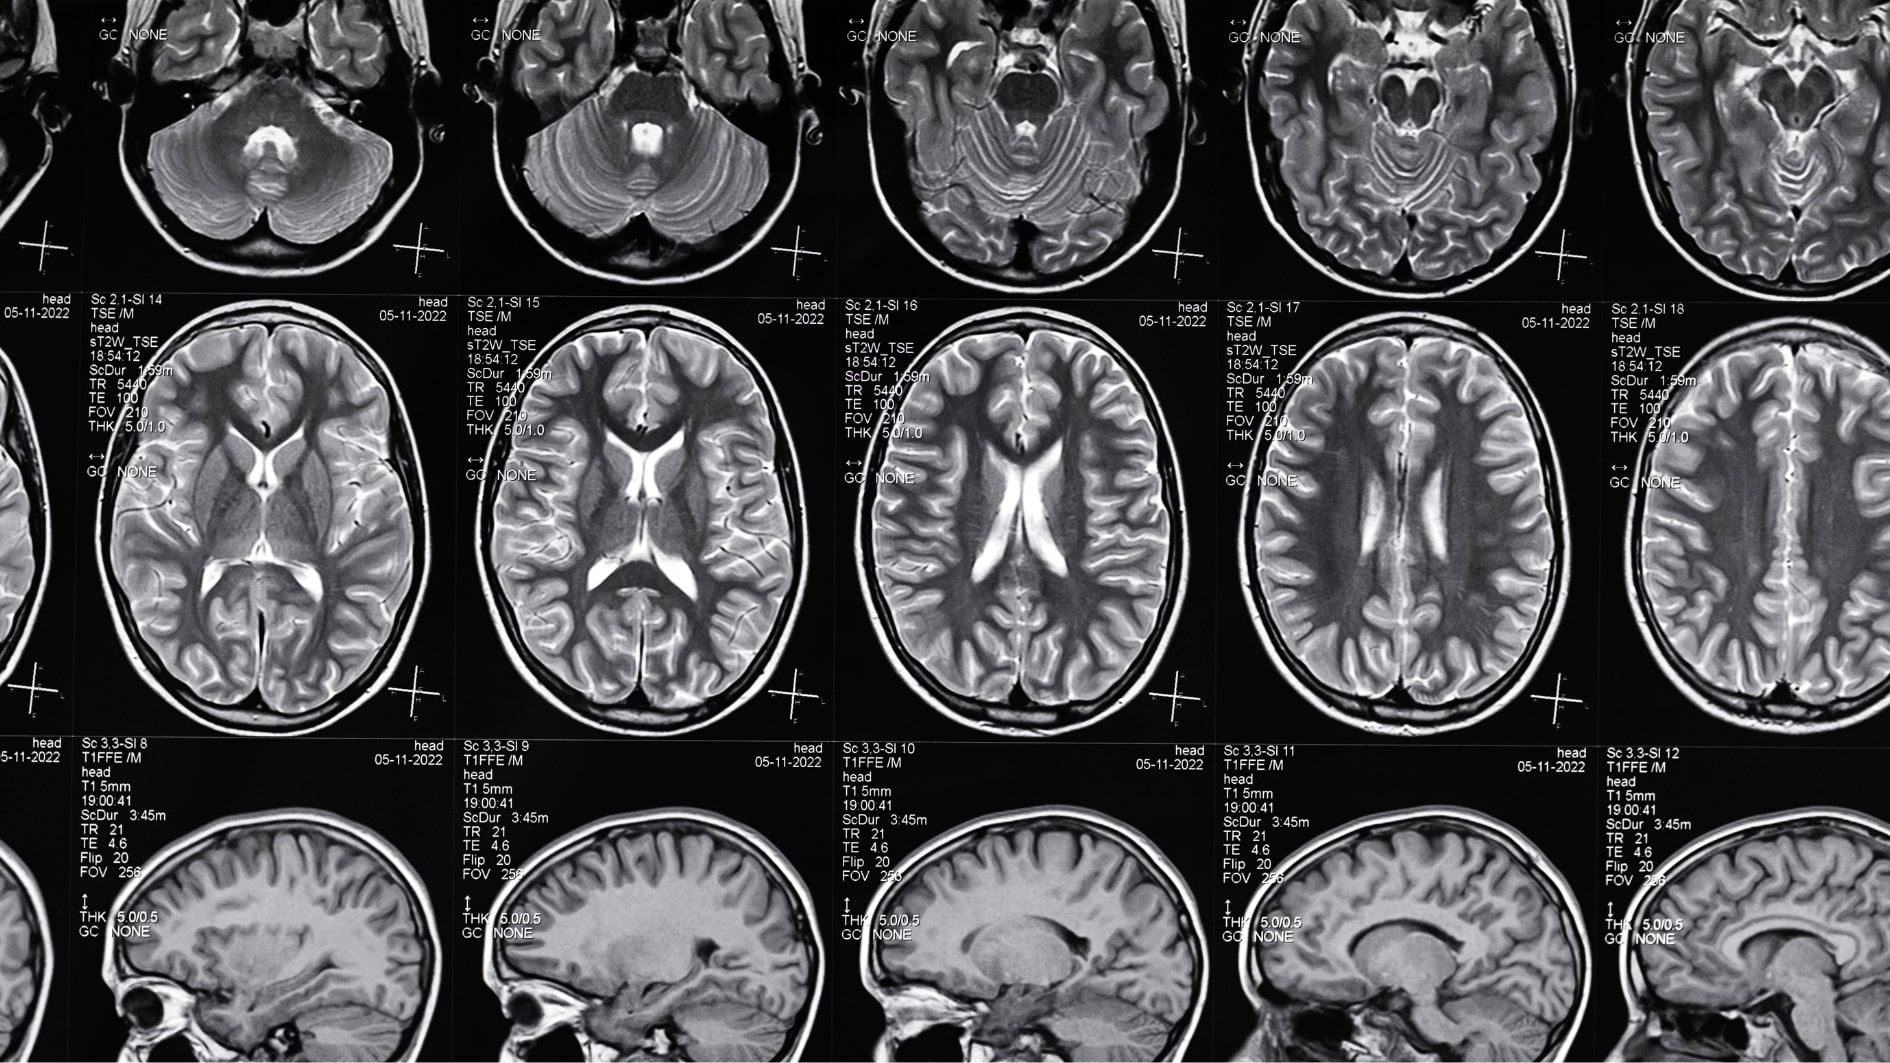

A ressonância magnética crânio-encefálica é um exame de neuroimagem que permite identificar áreas de cérebro anormais que poderão, potencialmente, ser responsáveis pelas crises epiléticas. As lesões responsáveis pelas epilepsias focais são muitas vezes pequenas e subtis podendo facilmente passar despercebidas. Assim, a ressonância magnética deve ser feita num aparelho de alta resolução, com protocolos específicos e deve ser analisada por um neurorradiologista com experiência na área da epilepsia. Em determinadas situações, pode ser realizada uma técnica designada ressonância magnética funcional, que permite identificar as áreas do cérebro responsáveis por funções importantes no dia-a-dia, como a capacidade de mover os membros ou falar, e ainda verificar a sua relação com a área cerebral anormal. Assim, é possível avaliar a segurança de uma potencial cirurgia com intenção curativa.